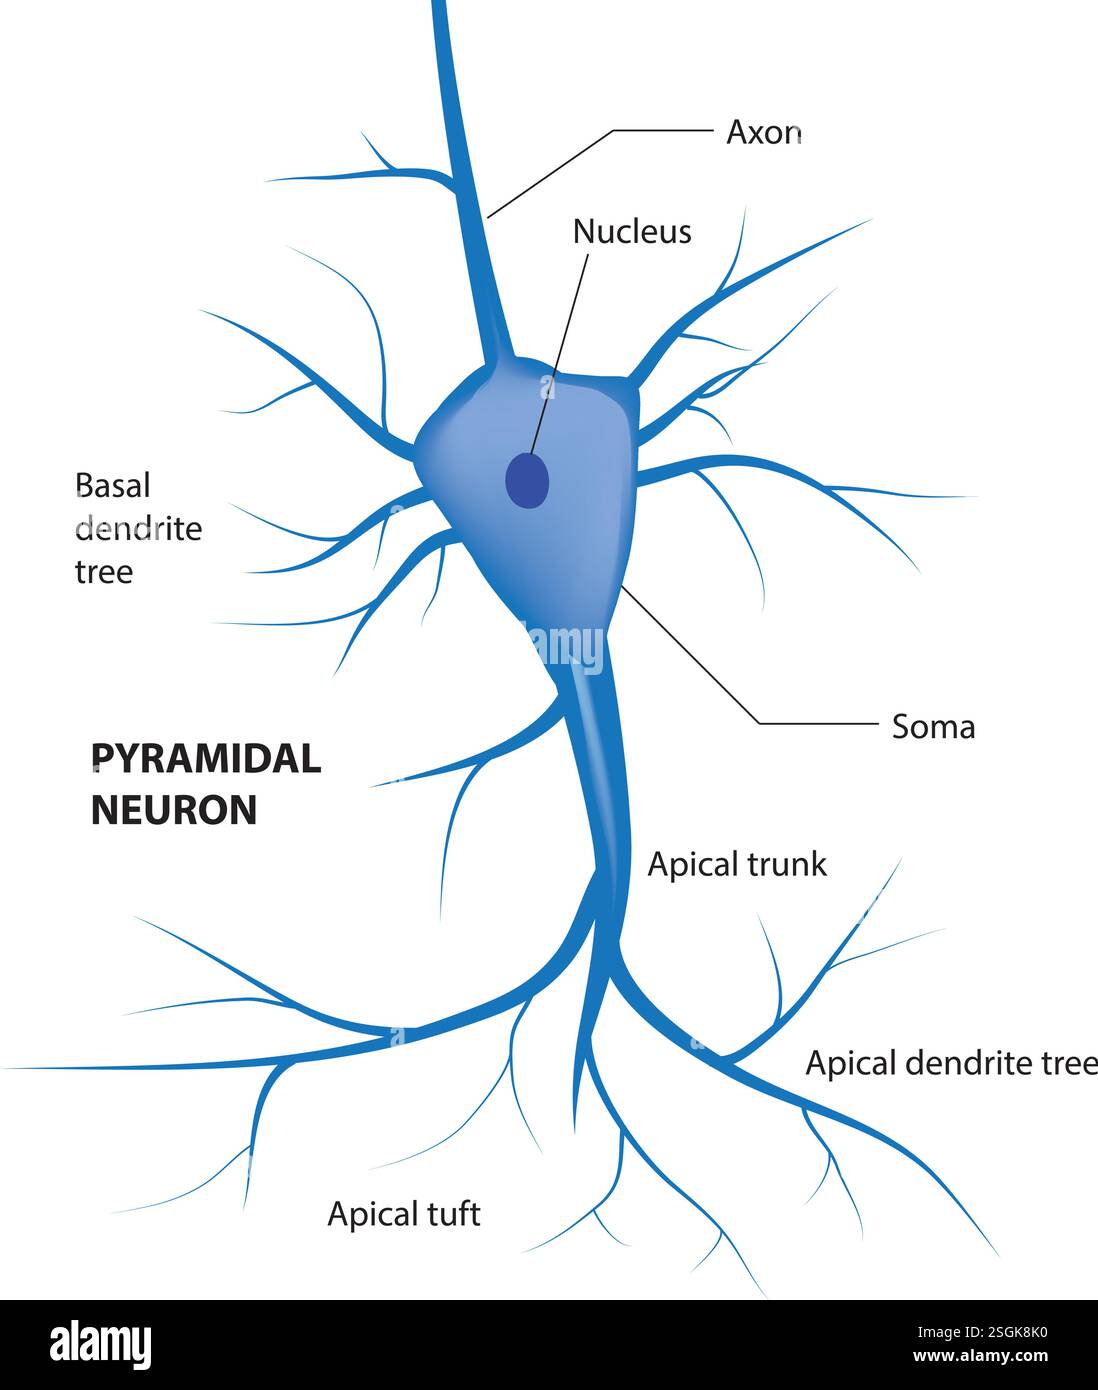

RF2J7343T–Tipi di neuroni: Cellule piramidali della corteccia cerebrale, cellule Purkinje della corteccia cerebrale, cellule olfattive dell'epitelio olfattivo